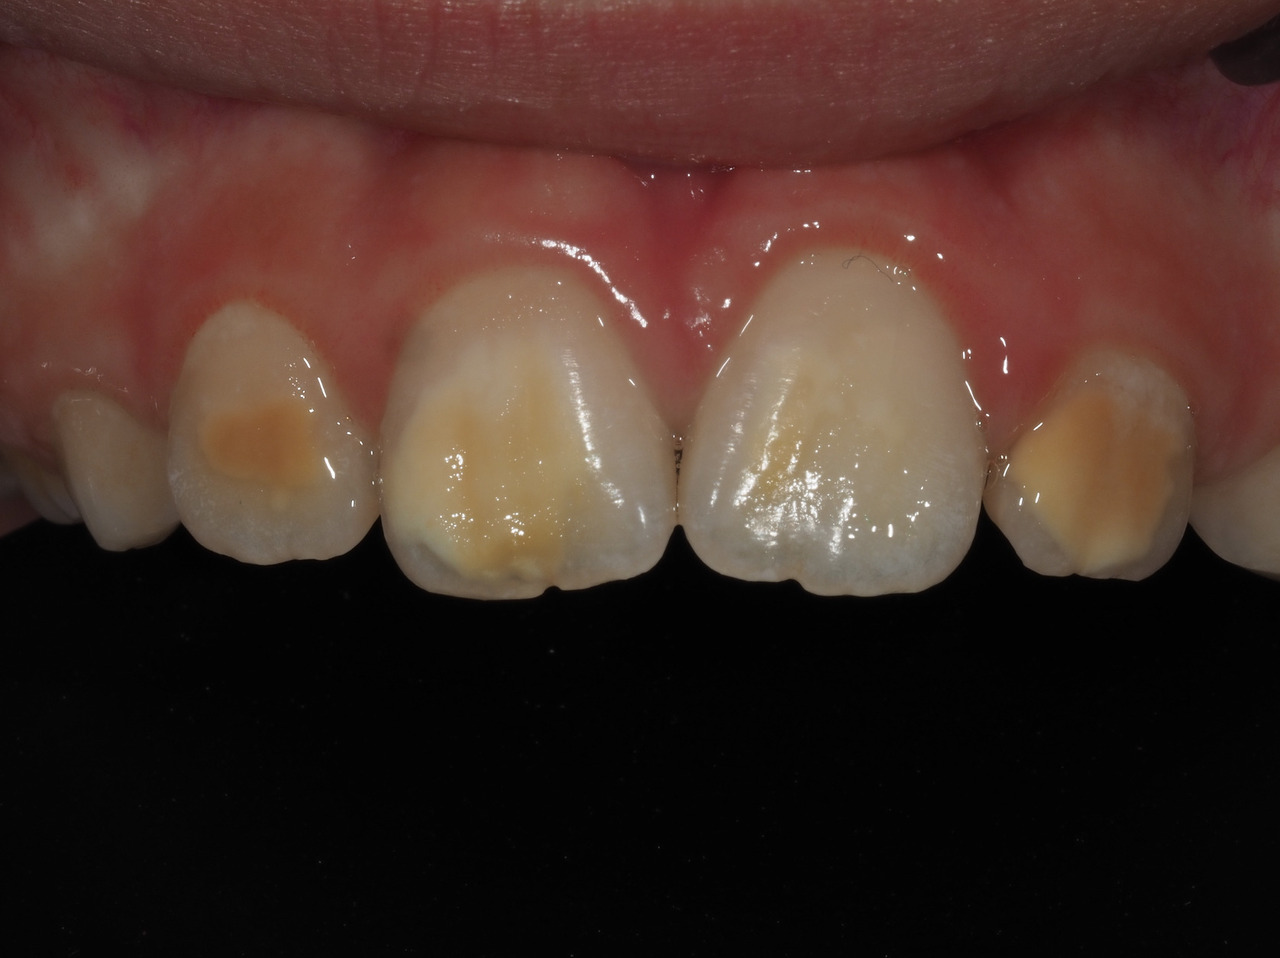

Les dents antérieures ont rarement des pertes de substance ou des lésions carieuses ; la problématique réside dans l’aspect disgracieux des lésions (fig. 3). Pour la gestion de ces taches, des traitements plus ou moins invasifs pourront être envisagés seulement pour des enfants avec une bonne hygiène bucco-dentaire et une coopération suffisante : micro, macro-abrasion, ou infiltration résineuse.9 Ils sont utilisés seuls ou en combinaison et nécessitent parfois la réalisation d’une restauration collée en résine composite (fig. 4).

Le diagnostic repose sur l’observation clinique : des opacités (taches) blanches, beiges ou brunes de taille variable sont présentes et visibles sur les dents atteintes (fig. 1, 2 et 3). Les opacités, bien démarquées, sont présentes dès l’éruption de la dent et leur taille ne se modifie pas dans le temps. Cependant, l’émail étant plus fragile, des fractures amélaires post-éruptives sont observées, entraînant des pertes de substance surtout au niveau des molaires qui sont soumises aux forces de mastication. L’atteinte est asymétrique, c’est-à-dire que pour un même patient sa sévérité peut varier d’une dent à l’autre, allant d’une absence d’atteinte à une perte de substance importante, en passant par une dyschromie discrète. Si une tache est observée sur une incisive permanente, il est important d’examiner les molaires permanentes. Le médecin généraliste doit alors évoquer une anomalie de structure dentaire et orienter le patient vers un chirurgien-dentiste. Celui-ci confirmera le diagnostic de MIH ou établira un autre diagnostic. Les diagnostics différentiels sont :